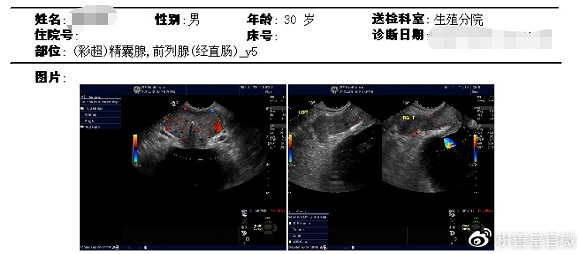

附件:

前列腺大小为42*24*33mm,前列腺实质回声分布不均匀,可探及多个强回声;

超声提示:前列腺增大伴钙化灶